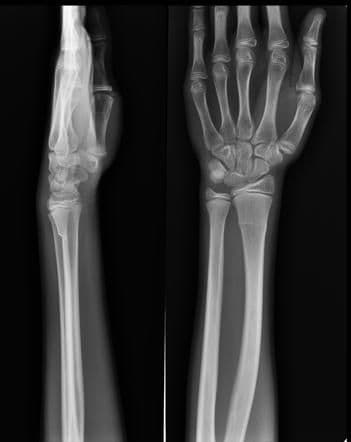

Torus Fracture - यात हाड तुटत नाही पण हाडाचा आकार बदलल्याने वेदना होतात.